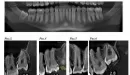

Да, припухлость в области восьмерки может быть связана с прорезыванием.

Что касается различных болей с изменением локализации, то по снимкам видно, что верхушки корней жевательных верхних зубов выступают в верхнечелюстную пазуху.

Рекомендую проконсультироваться у ЛОРа.